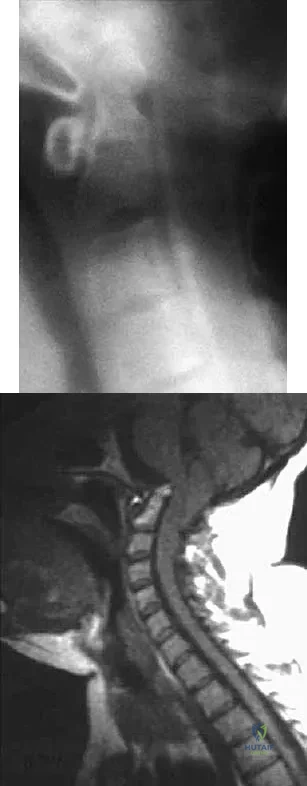

Figure 11 shows a consecutive sequence of MRI scans obtained in a 12-year-old boy who has had increasing lateral knee pain and catching for the past 6 months. Examination reveals pain localized to the lateral joint line. Range-of-motion testing reveals a 5-degree lack of full extension on the involved side. Plain radiographs and laboratory values are within normal limits. What is the most appropriate management?

Discoid menisci are rare causes of lateral knee pain in children. Various etiologies have been proposed, including failure of central absorption of the developing meniscus and hereditary transmission. Patients with discoid menisci have pain, clicking, and locking with a loss of active extension on range-of-motion testing. Classification of discoid menisci according to the Watanabe classification include complete, incomplete, and Wrisberg ligament type. The Wrisberg variant contains an abnormal posterior meniscal attachment. MRI is the diagnostic tool of choice, revealing a thick, flat meniscus generally seen in three consecutive MRI images. Symptomatic knees are often associated with a meniscal tear or degeneration and are managed with arthroscopic partial excision to a more normal shape (saucerization). Vandermeer RD, Cunningham FK: Arthroscopic treatment of the discoid lateral meniscus: Results of long-term follow-up. Arthroscopy 1989;5:101-109.